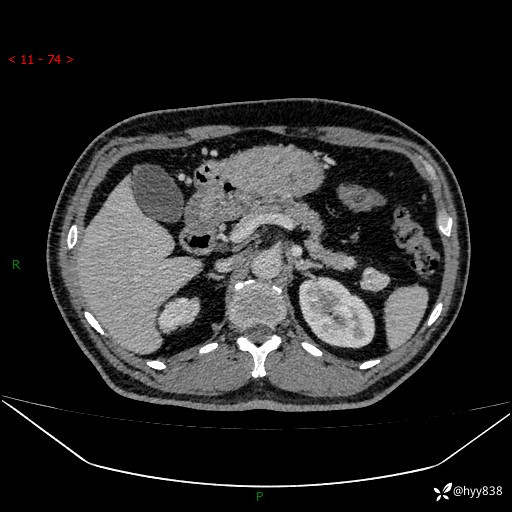

胰腺CT平扫

增强动脉期